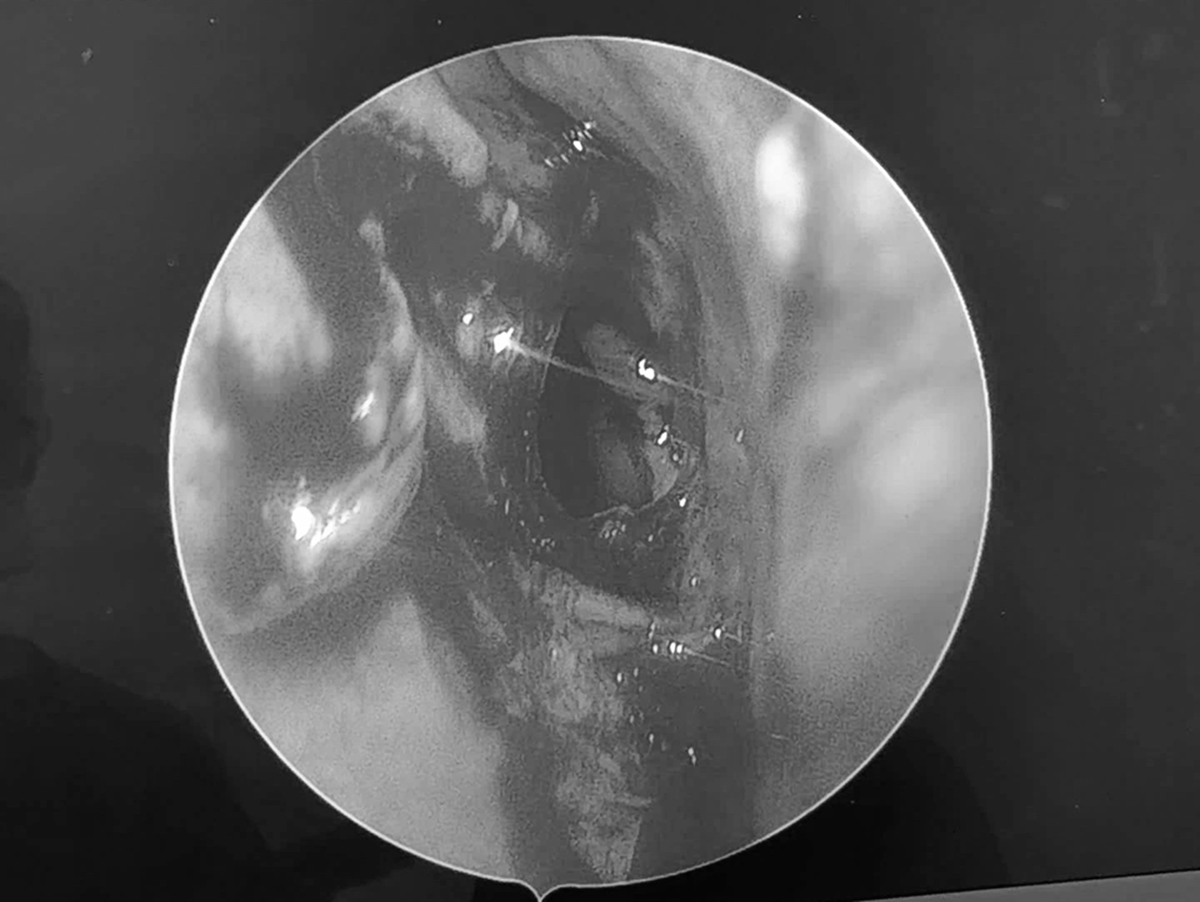

Đi khám, người đàn ông sốc nặng khi bác sĩ thấy thứ "đáng sợ" trong mũi mình- Ảnh 1.

Kết quả chụp chụp MRI cho thấy cụ B.Ph. có một khối u nhầy xoang bướm. Ảnh: Báo Thanh Niên.

Kết quả MRI cho thấy không ghi nhận xuất huyết, nhồi máu hay khối u não mà xác định bệnh nhân bị u nhầy xoang bướm gây lan vào đỉnh hốc mắt trái.

Sau khi thăm khám, bác sĩ Nguyễn Thanh Tiên cùng ê kíp đã tiến hành phẫu thuật mở xoang bướm và lấy sạch bệnh tích, dẫn lưu bằng phương pháp nội soi mũi xoang.